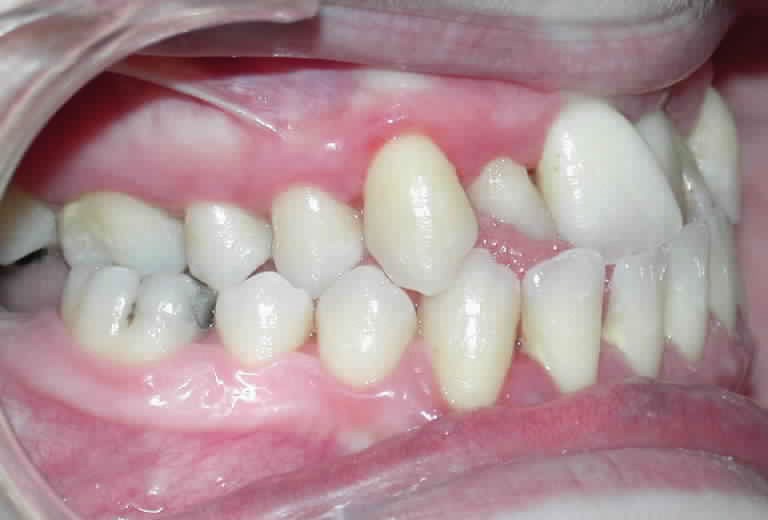

Cette patiente est venue consulter pour son occlusion inversée et ses importantes malpositions dentaires antérieures associées à la perte d’une dent et à des problèmes parodontaux.

• Malocclusion de classe III d’Angle par rétroalvéolie maxillaire,

• endoalvéolie maxillaire avec occlusion inversée antérieure et bilatérale,

• infraclusion incisive,

• fortes malpositions des incisives supérieures (dont 22 qui est en rotation axiale disto-palatine de 90°), • dysharmonie dento-dentaire (12 en « grain de riz » est aussi en rotation marginale disto-palatine de 45°),

Le sourire est inesthétique (fig. 3) et de profil il existe une rétrochéilie supérieure (fig. 2).